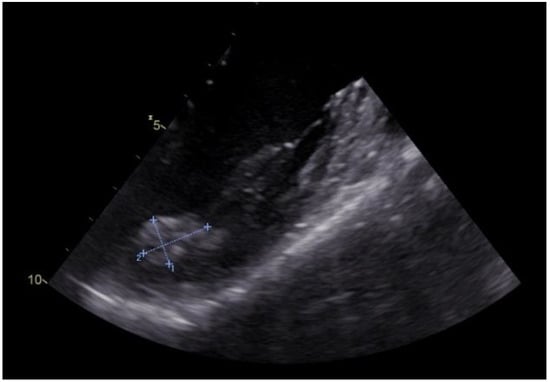

We present the case of a 42-year-old woman with no significant cardiovascular symptoms admitted to the hospital for further medical investigations after the incidental discovery of a left ventricular mass during a routine TTE presented in Figure 1.

Figure 1. Two-dimensional transesophageal echocardiography of the tumour in the left ventricle and papillary muscle at the base of the anterolateral papillary muscle (orange arrow, tumour; blue arrow, anterolateral papillary muscle).

The patient had a personal history of euthyroid autoimmune thyroiditis and minor beta-thalassemia and no history of surgical interventions. Worth mentioning in her family history is her father’s pulmonary neoplasm, diagnosed at the age of 57. The TTE at admission revealed no valvular dysfunction, a left ventricle (LV) with normal systolic function, with a left ventricle ejection fraction (LVEF) of 60%, but the presence of a hyperechogenic, homogenous mass in the LV, at the base of the anterolateral papillary muscle, apparently without myocardial invasion, immobile, of approximately 23/11 mm.